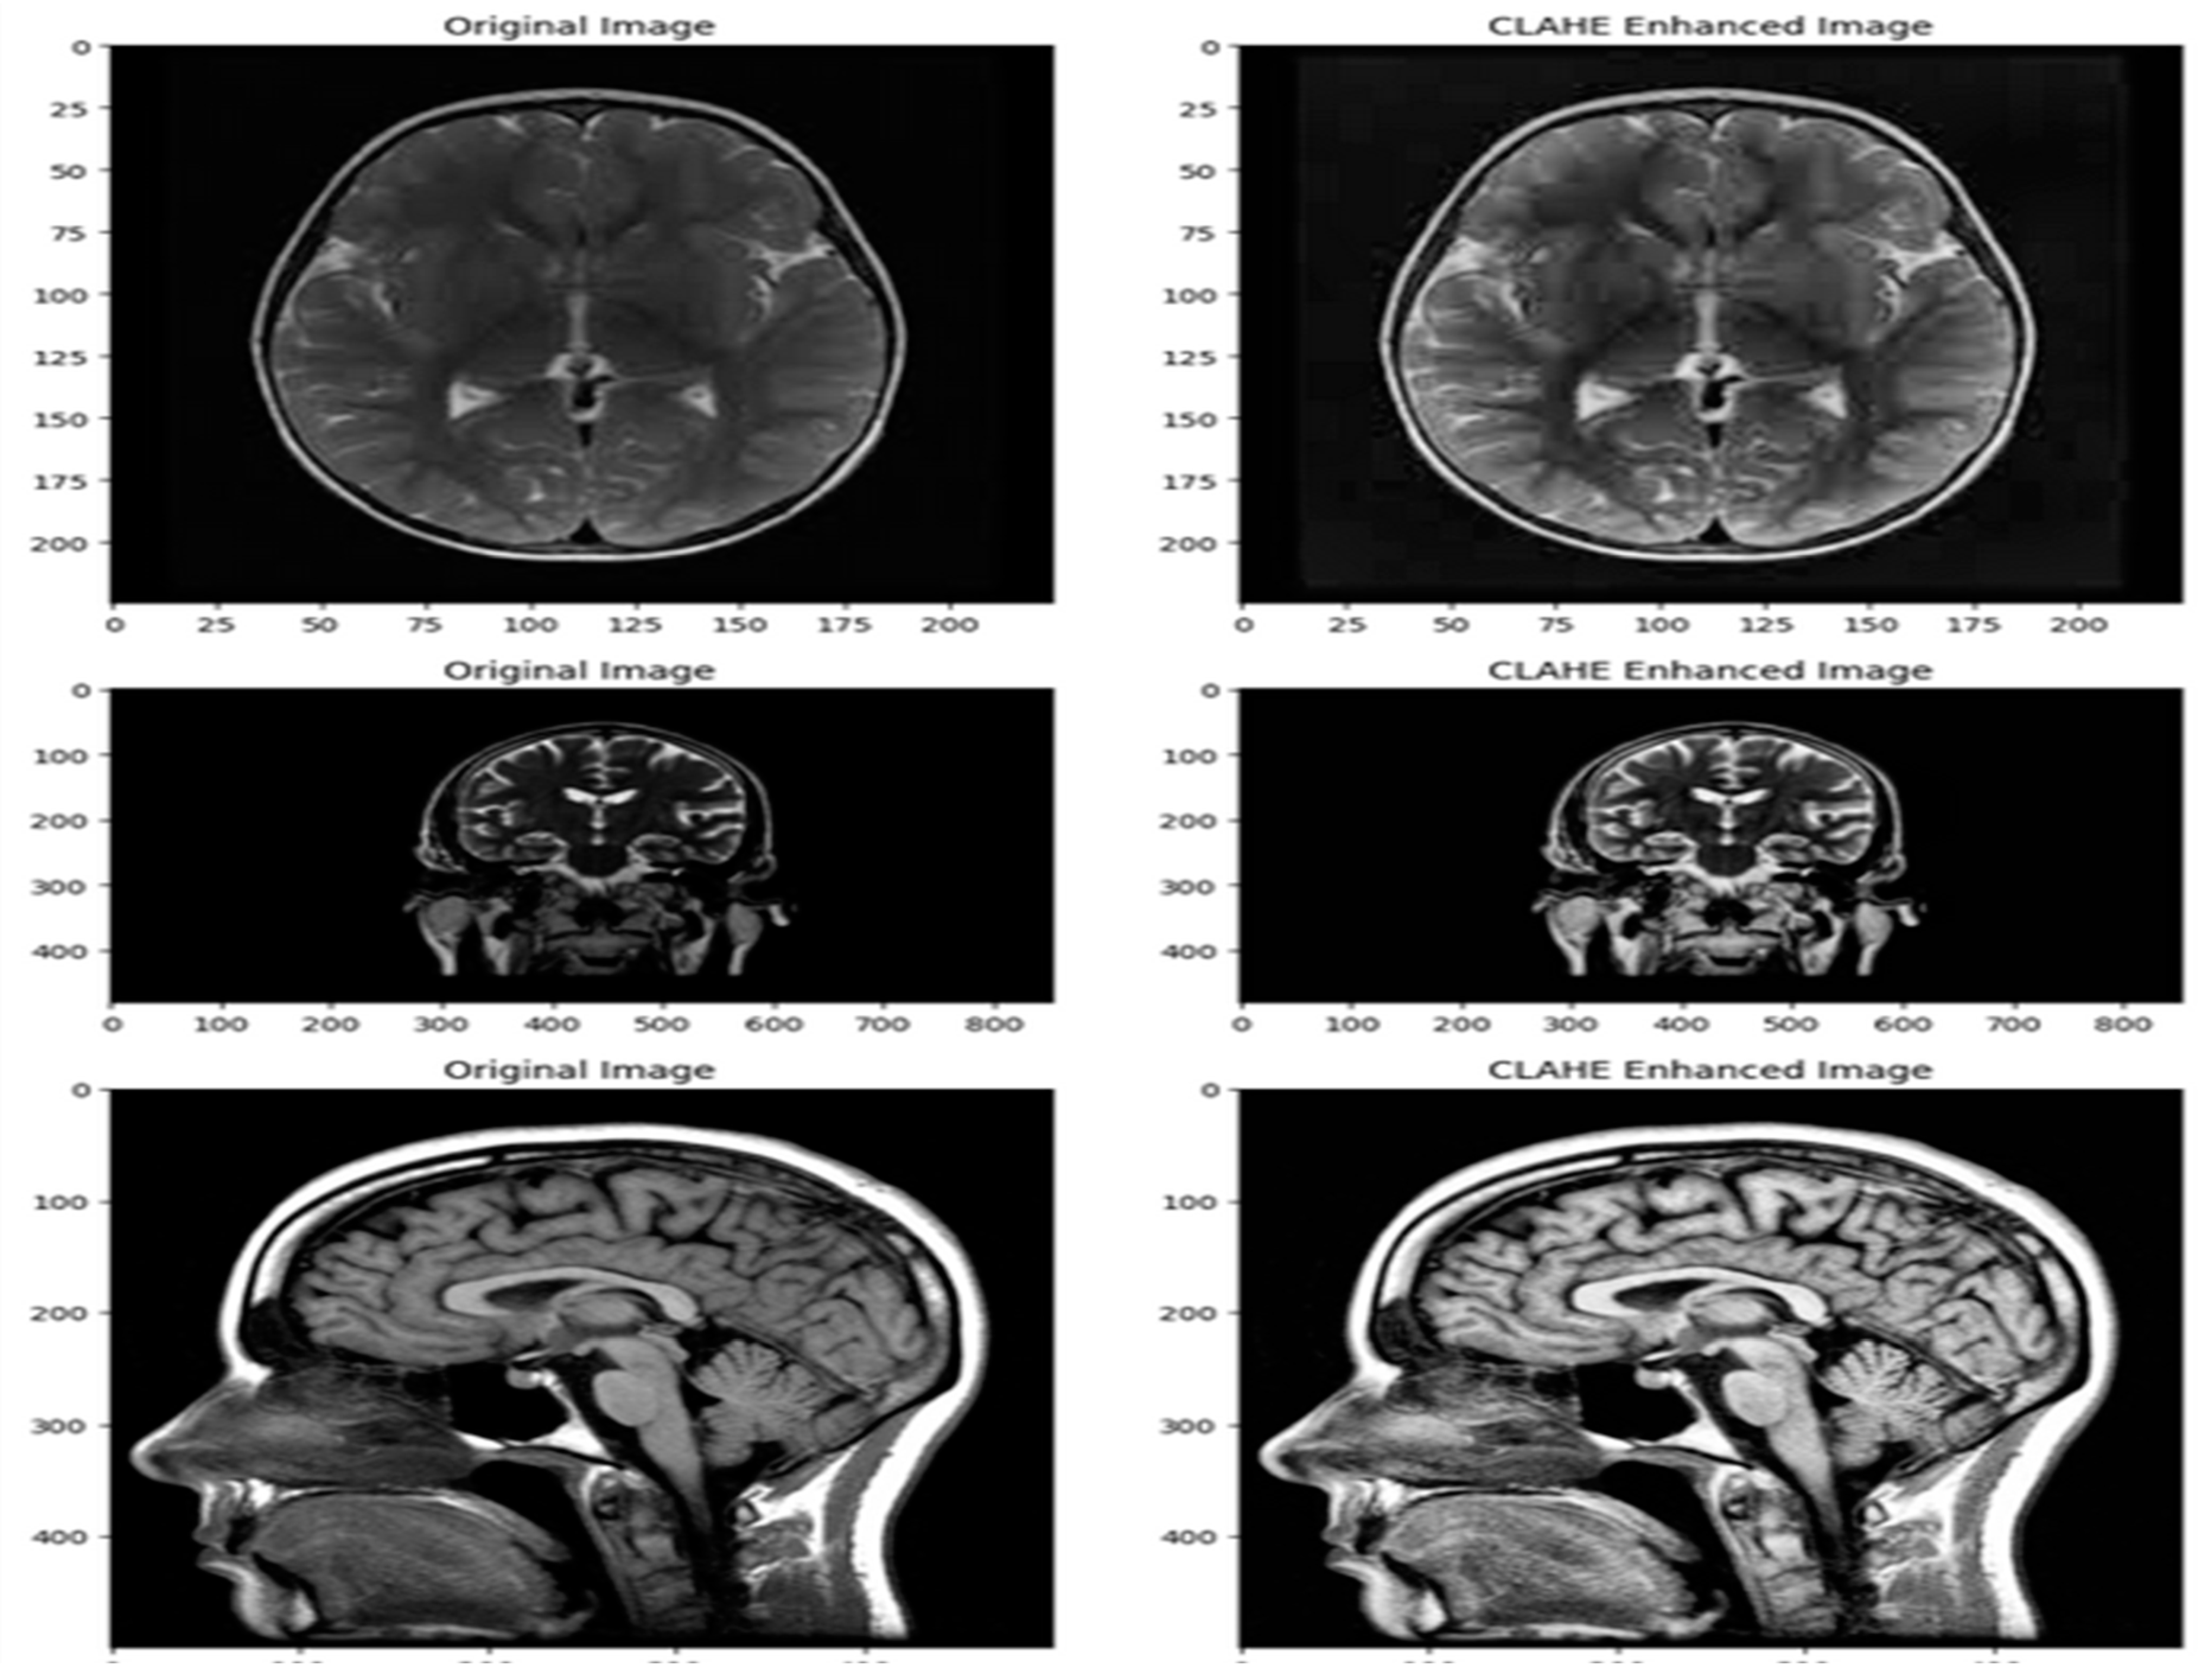

- Pre-processing the MRI Images using Contrast Limited Adaptive Histogram Equalization (CLAHE).

3.2. Data Pre-Processing